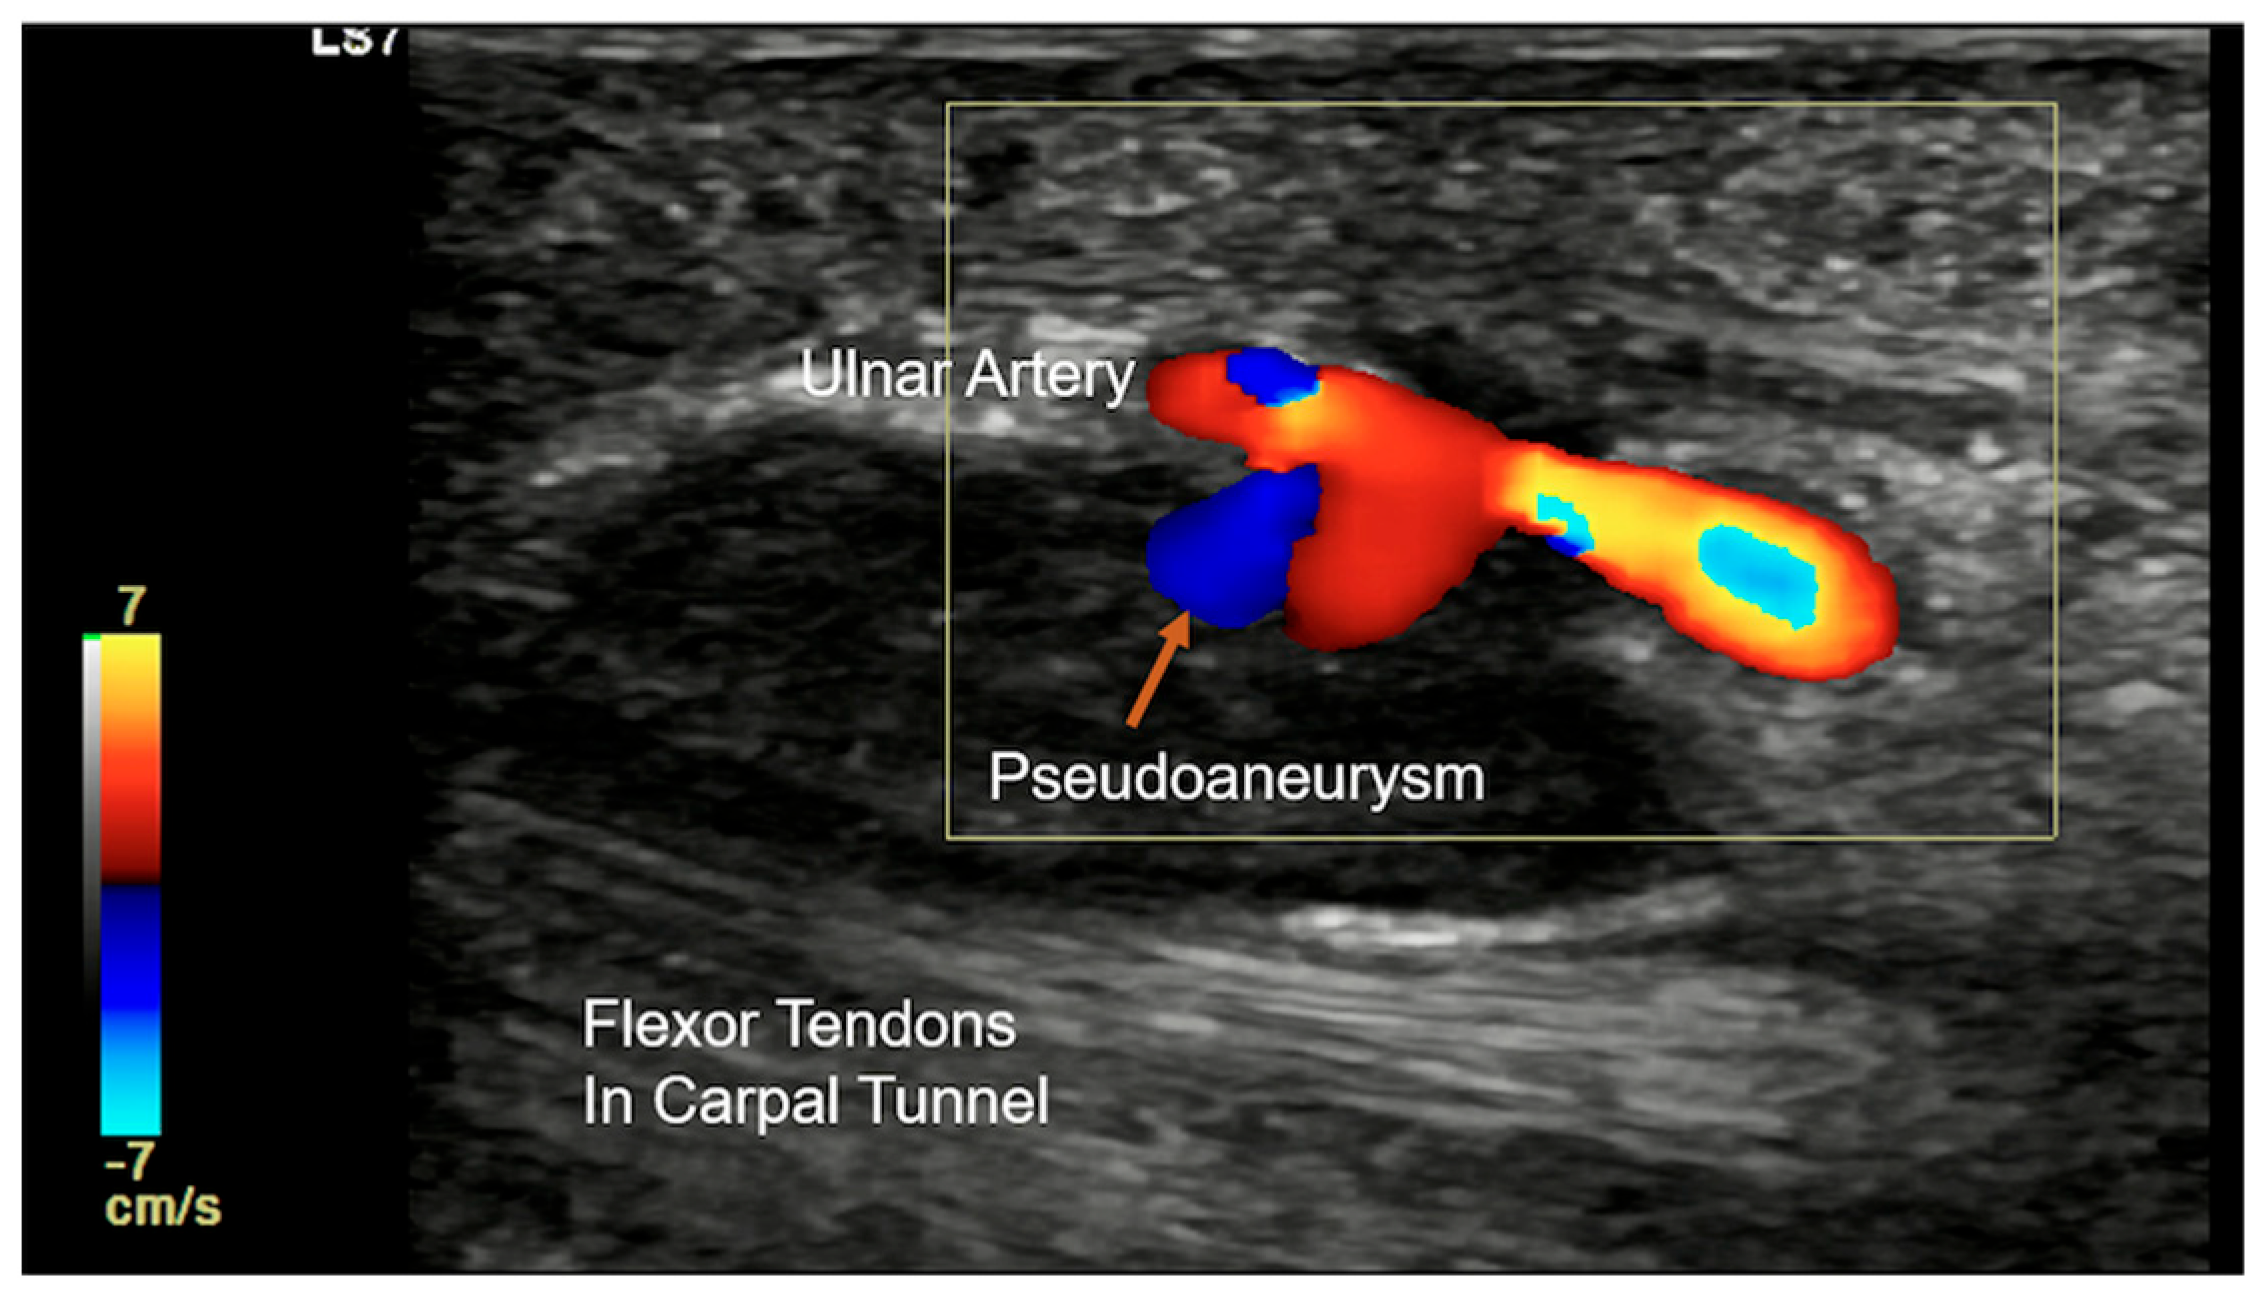

Other pathological conditions affecting Guyon’s canal include vascular abnormalities such as arteriovenous malformation (Figure 15), ulnar artery thrombosis, tortuosity (Figure 16), or aneurysms. Ultrasound imaging will show hypoechoic or anechoic mass with vascular flow seen on Doppler imaging in cases of aneurysm with absence of flow in a case of thrombosis. On MRI, thrombosis is seen as low or high signal intensity within the vessel lumen on both T1- and T2-weighted images, depending on duration. Aneurysms appear as well-circumscribed lesions, potentially with signal voids due to high flow. Pseudoaneurysm will show the presence of adjacent soft-tissue mass in close approximation with the lumen [23].

Guyon’s canal can be affected by post-operative scar, rheumatoid arthritis causing pannus formation, or trauma-related lesions. Traumatic injuries in Guyon’s canal include both sharp and blunt trauma. Sharp injury is not uncommon and can result in Ulnar nerve transection and arterial injury. Depending upon the extent, the nerve may be partially or completely lacerated. Complete laceration can lead to the formation of stump neuroma, which appears to be a bulbous enlargement of the stump of the lacerated nerve (Figure 17). Blunt injury can involve bone as well as soft-tissue structures [24]. Hook of hamate fracture can occur as a result of a fall or in sports injury from racquets or bats while swinging. If occult on the standard radiograph, a carpal tunnel view will be able to demonstrate the fracture. CT and MRI can be considered if the radiograph is negative and there is a high suspicion of injury. Repeated trauma in this region in persons using a hammer/vibrating tool and in athletes is also seen (see Section 4.2). Repetitive trauma to the ulnar artery against the hook of the hamate can cause the formation of an aneurysm/pseudo-aneurysm or thrombosis (Figure 18) [25].

Colour Doppler longitudinal ultrasound image showing ulnar arterial pseudoaneurysm (orange arrow) in a case of hypothenar hammer syndrome.